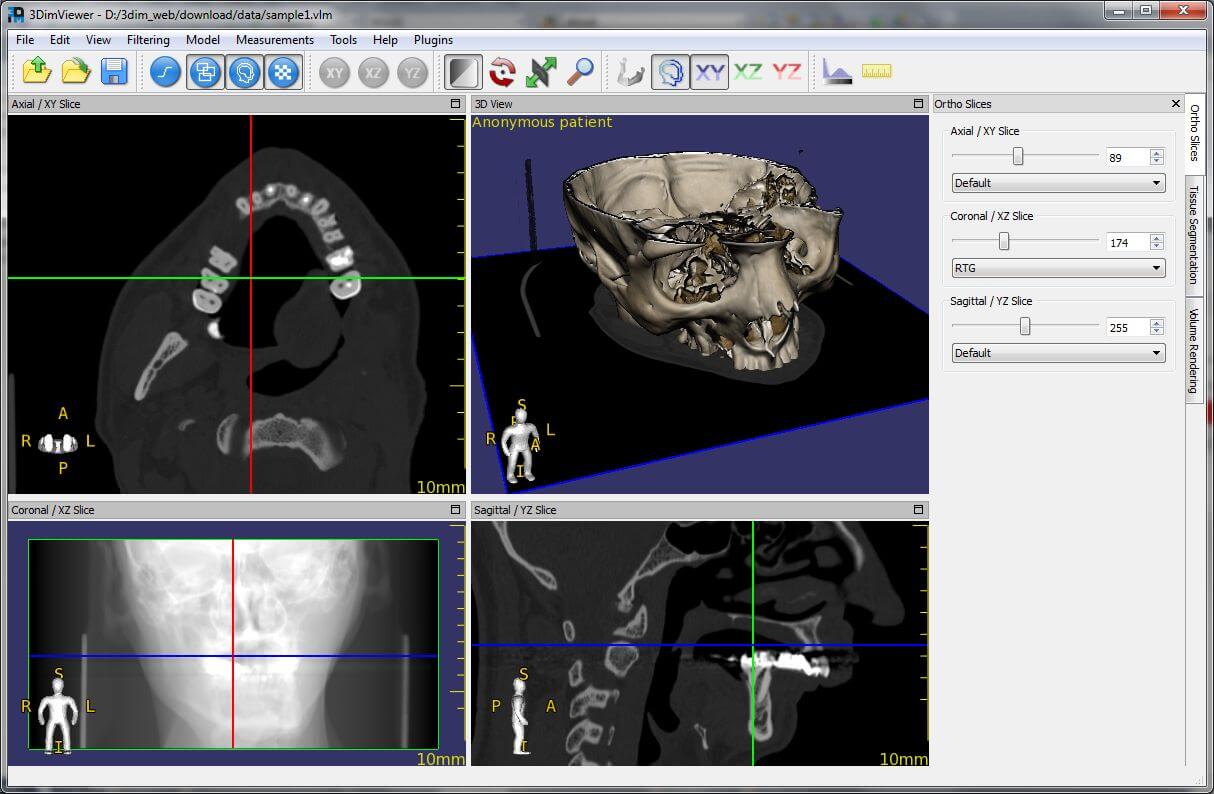

This is a lightweight application that is great for beginners who are learning to use a DICOM viewer. Its biggest advantage is that it can be run on multiple operating systems. It offers multiplanar views, MIP and volume rendering, but image editing and exporting are not possible.

| 7. | 3DimViewer | Windows, Mac OS X, Linux | Not available | Y | Y | Y | N.A. | N.A. | N.A. | Free license |